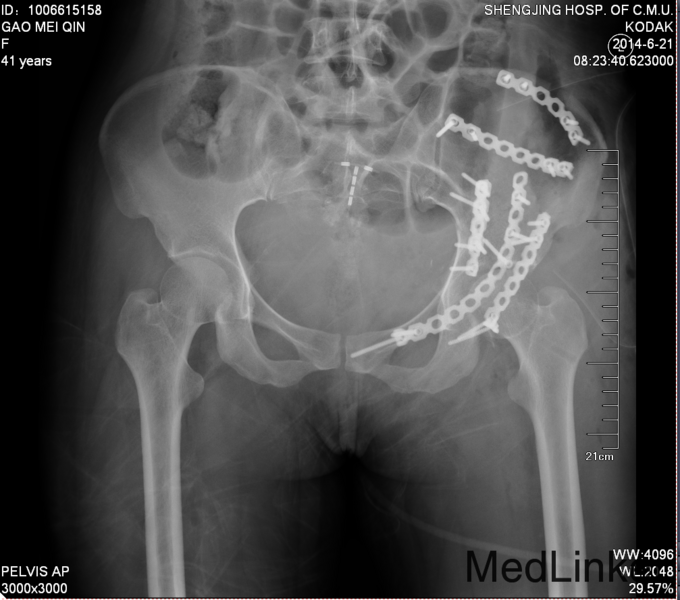

主诉:车祸外伤后左髋部疼痛伴活动受限4天 患者于2014年6月12日早6点左右被皮卡车撞伤,伤后患者出现一过性昏迷,被急诊送往当地医院,行DR及CT检查后,诊断为:左髋臼骨折,于当地医院骨科行骨牵引、抗炎补液等对症治疗后,现为求进一步治疗转入我科,患者病来无头晕头痛,无恶心呕吐,已排气排便.

入院后请神经外科会诊,请麻醉科会诊评估手术风险,查无明显手术禁忌症后,全麻下行左髋臼骨折切开复位内内固定术,术后留置引流,术后3天拔除引流管,切口换药无红肿渗出,术后4天转入当地医院继续治疗。

患者左髋臼骨折,髋臼骨折出血量大,应用自体血回输继续。术中注意血管及神经的副损伤。